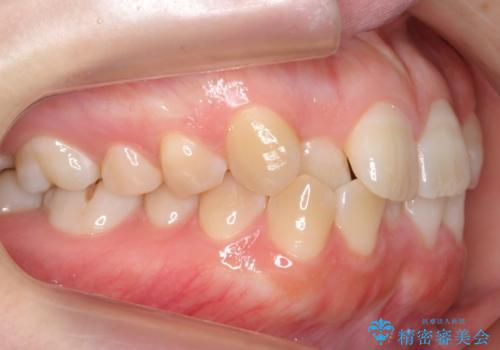

よくある悩み 前歯が裏に2本入っているのを治したい

- 前歯が2本裏に入ってしまっているのを治したいとのことでした。

最小限の抜歯により矯正ができたと、喜んでいただきました。